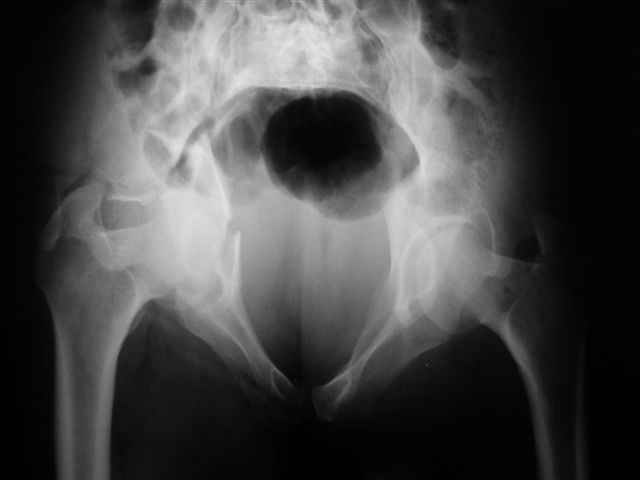

Уважаемые коллеги,43 летний мужчина, попав в автоаварию 13.10.2004, получил оскольчатый перелом обеих колонн левой вертлужной впадины.

На рентгенограммах - высокий двухколонный перелом вертлужной впадины с нарушением конгруэнтности, имеется обратная клиновидность суставной щели.

Спасибо за комментарии и рекомендации. Откровенно говоря, больного я прооперировал на прошлой неделе, через 5 дней после аварии и проблем с ним пока никаких нет, на удивление при достаточно обширной диссекции (илиофеморальный доступ) болей практически нет, так что больной самостоятельно садится в кровати, выполняет активные движения в оперированном суставе, сгибая до 60 градусов пока, далее с ассистенцией.

Причиной обращения к сообществу были возникшие непосредственно после операции сомнения и разочарования полученным качеством репозиции: а надо ли было трогать перелом вообще, репозиция передней колонны технически была очень сложна для меня, хотя реконструкции была в той же последовательности, что Д-р А.В.Рунков рекомендовал, в какой-то момент безуспешных манипуляций стал думать о *вторичной конгруэнтности*, которую не так давно обсуждали на

форуме и скелетном вытяжении. С репозицией и фиксацией задней колонны и отдельно задне-верхней стенки впадины проблем не возникло. Послеоп. Рг граммы в приложении. Если возникнут какие-либо дополнения или поправки - был бы признателен.